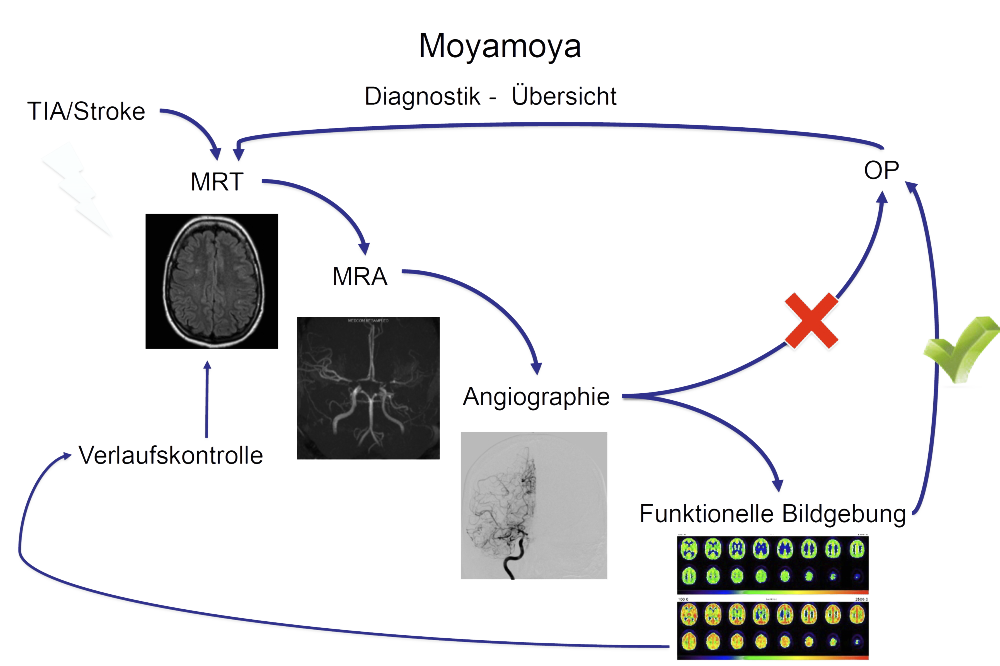

Hochauflösende MRT Bildgebung

In der MRT Bildgebung fertigen wir neben den Routine-Sequenzen der Schlaganfalldiagnostik spezielle hochauflösende Sequenzen auf einem modernen 3 Tesla Gerät an, die mit einer Auflösung von unter einem Millimeter die betroffenen Gefäßwände darstellen können. So kann eine mögliche Aktivität und ein Voranschreiten der Erkrankung erkannt und dementsprechend die weitere Behandlungs- und Kontrollstrategie angepasst werden. Im Rahmen unseres Forschungsschwerpunktes erforschen wir genau diese Veränderungen der Gefäßwände intensiv, um so das Voranschreiten der Erkrankung, sowie auch die Entstehung besser verstehen zu können.